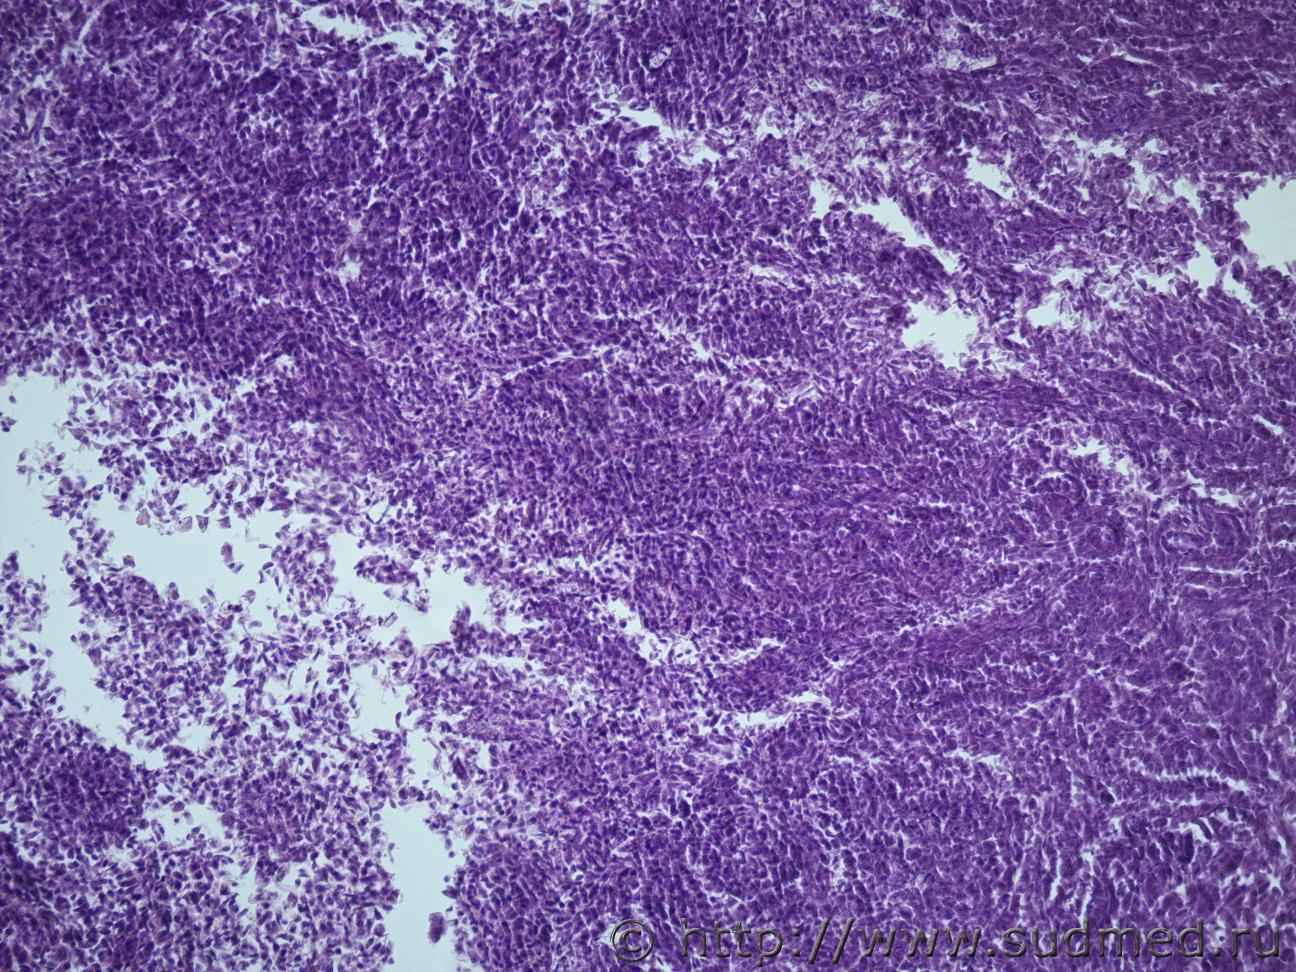

Жен 62 года. На задней поверхности левой почки желтовато-сероватый участок 1на1 см, творожистой консистенции.Судебная медицина - Прикрепленное изображение Судебная медицина - Прикрепленное изображениеСудебная медицина - Прикрепленное изображениеСудебная медицина - Прикрепленное изображениеСудебная медицина - Прикрепленное изображение

Почечноклеточный рак,другого не придумал. wink.gif

Меня тоже посещает мысль, что это почечно-клеточный рак, папиллярный тип)))